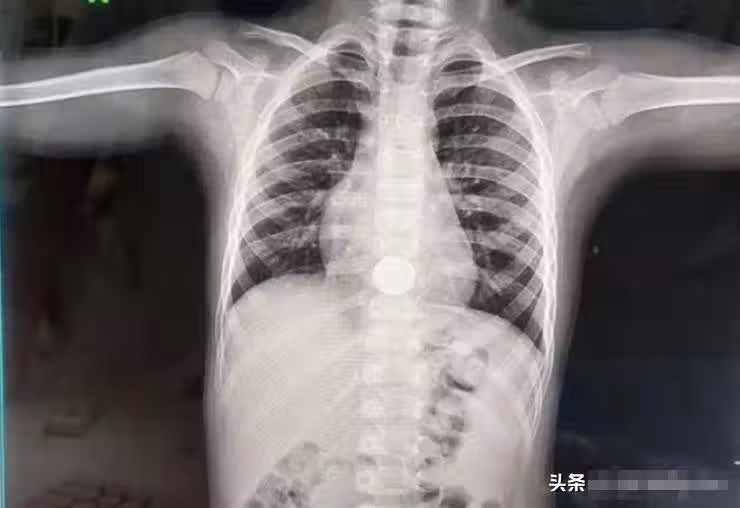

媽媽聽完嚇出一身冷汗,孩子說 他剛才吃了一枚硬幣,自己是不是就可以生下硬幣了 。

媽媽都沒來得及回答,便趕緊連夜把孩子送進了醫院。好在經過醫生耐心細致的拍片、檢查,最終通過無創手術,硬幣被順利地取了出來。